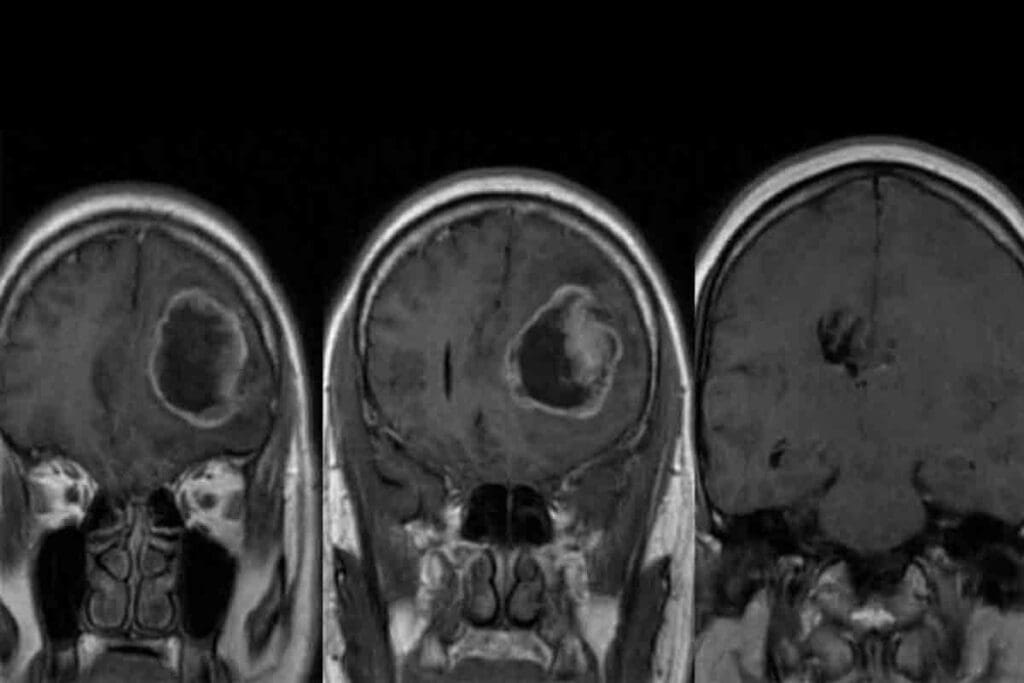

Imaging Studies (MRI, CT Scans)

Imaging is vital for diagnosing pediatric GBM. MRI and CT scans help us see the tumor in the brain. MRI gives us clear images of soft tissues, showing the tumor’s size and where it is.

Biopsy and Histopathological Evaluation

A biopsy is key to confirming GBM. We take tissue samples during surgery. Looking at these samples under a microscope helps us spot the tumor’s unique features.